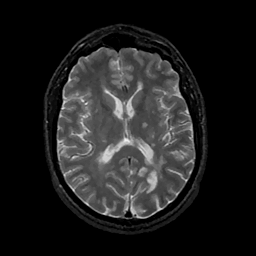

MR Study #11, May 5, 1991 -- Slice #28